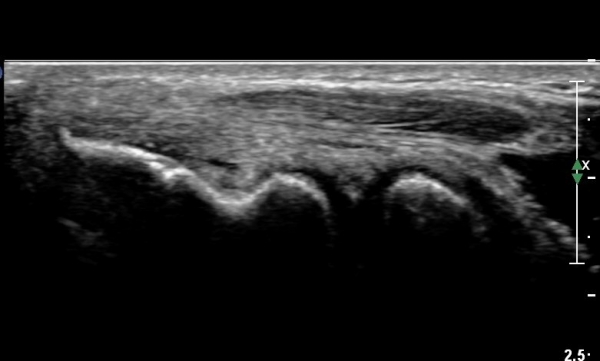

¿Ü»ó°ú Á¾´Ù¸é°Ë»ç¿¡¼­ ªÀº¼Õ¸ñ½ÅÀü°Ç ºÎÂøºÎ¿¡ ±¹¼ÒÀûÀÎ Àú¿¡ÄÚ º¯È­°¡ °üÂûµÊ(»çÁø 1, 2).